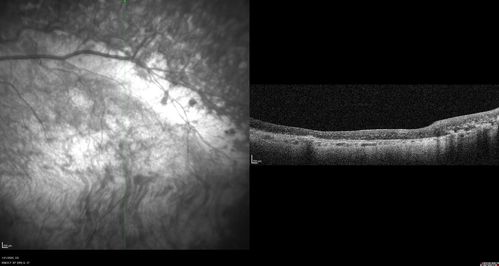

Enhanced S Cone Syndrome - Goldmann Favre - NR2E3 Mutation

82 year old man with poor vision for many years. VA HM OD, 5/200 OS. Diagnosed at age 12 with retinitis pigmentosa. Nystagmus.